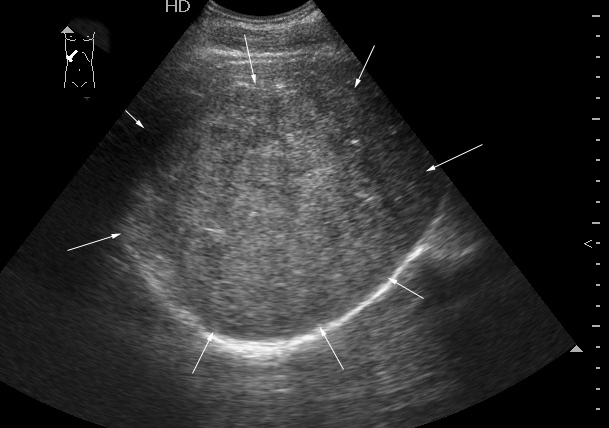

После КТ хирурги заказали дренирование "абсцесса".

Выполнена диагностическая пункция из 4х участков, получена только кровь.

На следующий день сонографическая картина немного изменилась:

Какие мысли?

на узи на абсцесс не похоже, образование солидное ----гепатома?

Гигантская капилярная гемангиома печени.